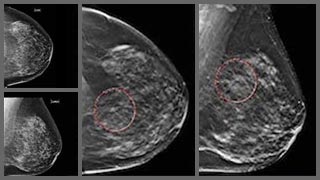

Predicting Cancer using mammogram data A mammogram is an x-ray picture of the breast.

It can be used to check for breast cancer in women who have no signs or symptoms of the disease. It can also be used if you have a lump or other sign of breast cancer. Screening mammography is the type of mammogram that checks you when you have no symptoms.

if you have been diagnosed with a tumor, the first step your doctor will take is to find out whether it is malignant or benign, as this will affect your treatment plan. In short, the meaning of malignant is cancerous and the meaning of benign is non-cancerous. Learn more about how either diagnosis affects your health. Previously doctors do this using manually seeing mammogram photo